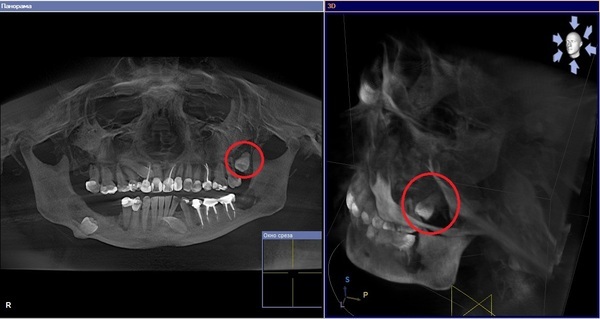

Первый снимок

Rentgenologia предоставляет нам зуб в толще кости верхней челюсти. Это 23 зуб - ретинированный и дистопированный клык верхней челюсти. На самом деле он не является запасным, потому что не прорезался из-за временного зуба (отмечен синей стрелочкой), который своевременно не удалили.

Второй снимок

Мистер R. в этом снимке показывает зуб в толще нижней челюсти. Это 35 зуб - ретинированный и дистопированный премоляр нижней челюсти, и он тоже не является запасным. Данный зуб должен был прорезаться, но имеет такое расположение, возможно, из-за нарушения эмбриогенеза.

Третий снимок

Клинический случай интересный, но охеревать как наш эксперт не стоит. В начале Rentgenologia обращает наше внимание на клык верхней челюсти. Это ретинированный и дистопированный 13 зуб. Он не является сверхкомплектным, а причина его расположения, скорее всего, такая же как и в предыдущем случае - нарушения эмбриогенеза. Данный клык давить на рядом расположенные не может, как утверждает охеревший эксперт, по причине того, что он плотно ограничен костью.

Далее автор "Запасные зубки" обращает наше внимание на, так называемые, говнюка и подлюку такую. На самом деле это - дистопированный и ретинированный 47 зуб, он же второй моляр нижней челюсти. Удаление такого зуба под общим наркозом очень круто на самом деле. Как минимум потому, что наркоз - общее обезболивание. Итого получается удаление зуба под общим общим обзеболиванием. Масло масленное какое-то.

После этого Rentgenologia пишет про чёрную дыру, из которой вынесли "нехилое", на его взгляд, количество кости, и после этого пациентка мол бегала от стоматологов как от Чикатилы. Знаете, я бы тоже бегал от стоматологов, которые говорят про чёрные дыры в моей челюсти, из которой выносят "нехилое" количество кости.

Потом автор столь занимательного поста ведёт речь про не менее интересную ситуацию. Действительно случай впечатляет. На снимке 28 зуб - ретированный и дистопированный третий моляр верхней челюсти, он же зуб мудрости. На самом деле, он не уплыл куда-то за под-из под (привет Rentgenologia). В стоматологии нет таких терминов. Этот зуб действительно расположен далеко от других зубов, и вовсе не находится чуть ли не в заподглазничном пространстве, ибо такого пространства в теле человека не существует вовсе.

Здесь Mr. R. пишет, что подобные случаи в стандартной стоматологии лучше не трогать. Здесь я соглашусь, за исключением одного - стандартной стоматологии нет в природе. Если бы она существовала, то появляется вопрос: какая стоматология не стандартная?

В конце обзора Rentgenologia показывает не самое интересное. Это оказывается 33 зуб - ретинированный и дистопировнный клык нижней челюсти. И действительно, люди об это узнают случайно, и в жизни этот зуб никак не беспокоит.

Четвертый снимок

Здесь автор "Запасные зубки" пишет про херню в подбородке. Эта херня - 33 зуб, ретинированный и дистопированный клык нижней челюсти. И знаете что я вам скажу по поводу этого этого? Я не был бы рад херне в подбородке.